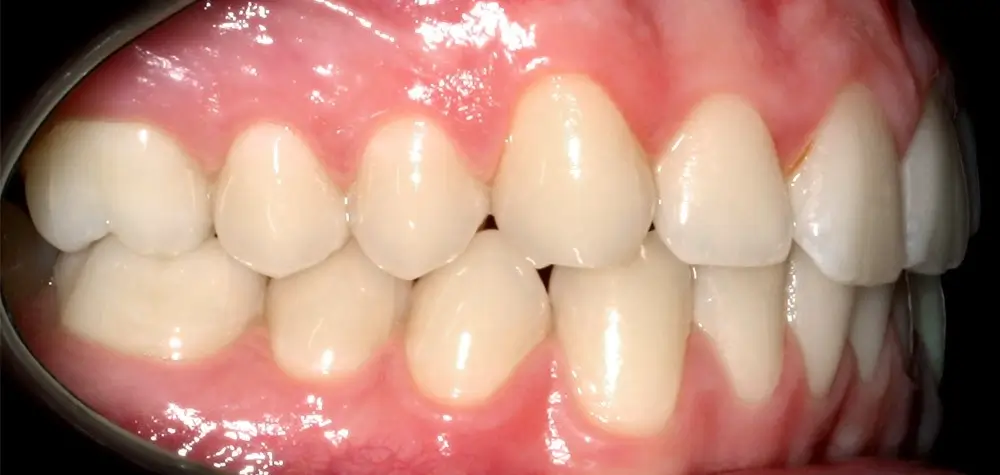

Скученность - Кейс 25

Эффективность устранения дефекта прикуса посредством элайнеров FlexiLigner.

Результаты лечения